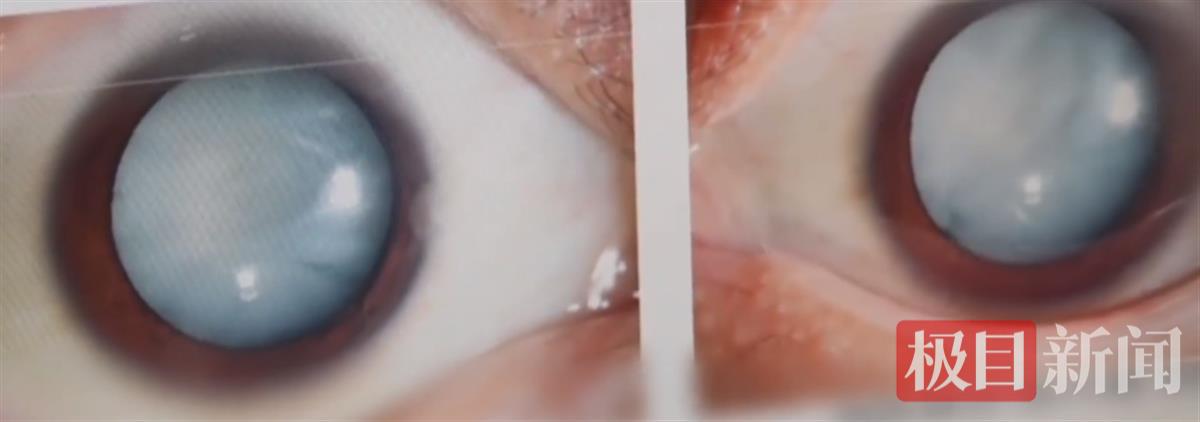

该院白内障与老视专科孙明副主任医师为小吴进行了详细检查,她发现,小吴的白内障情况极为严重,晶状体几乎完全浑浊,从外观上看,双眼毫无神采,瞳孔中央一片雪白。“双眼的晶状体几乎完全是浑浊的。即使在肉眼下,我们都看到他的双眼是无神的,瞳孔中央完全是白的。”孙明副主任医师表示。

小吴的双眼瞳孔中央已经全白